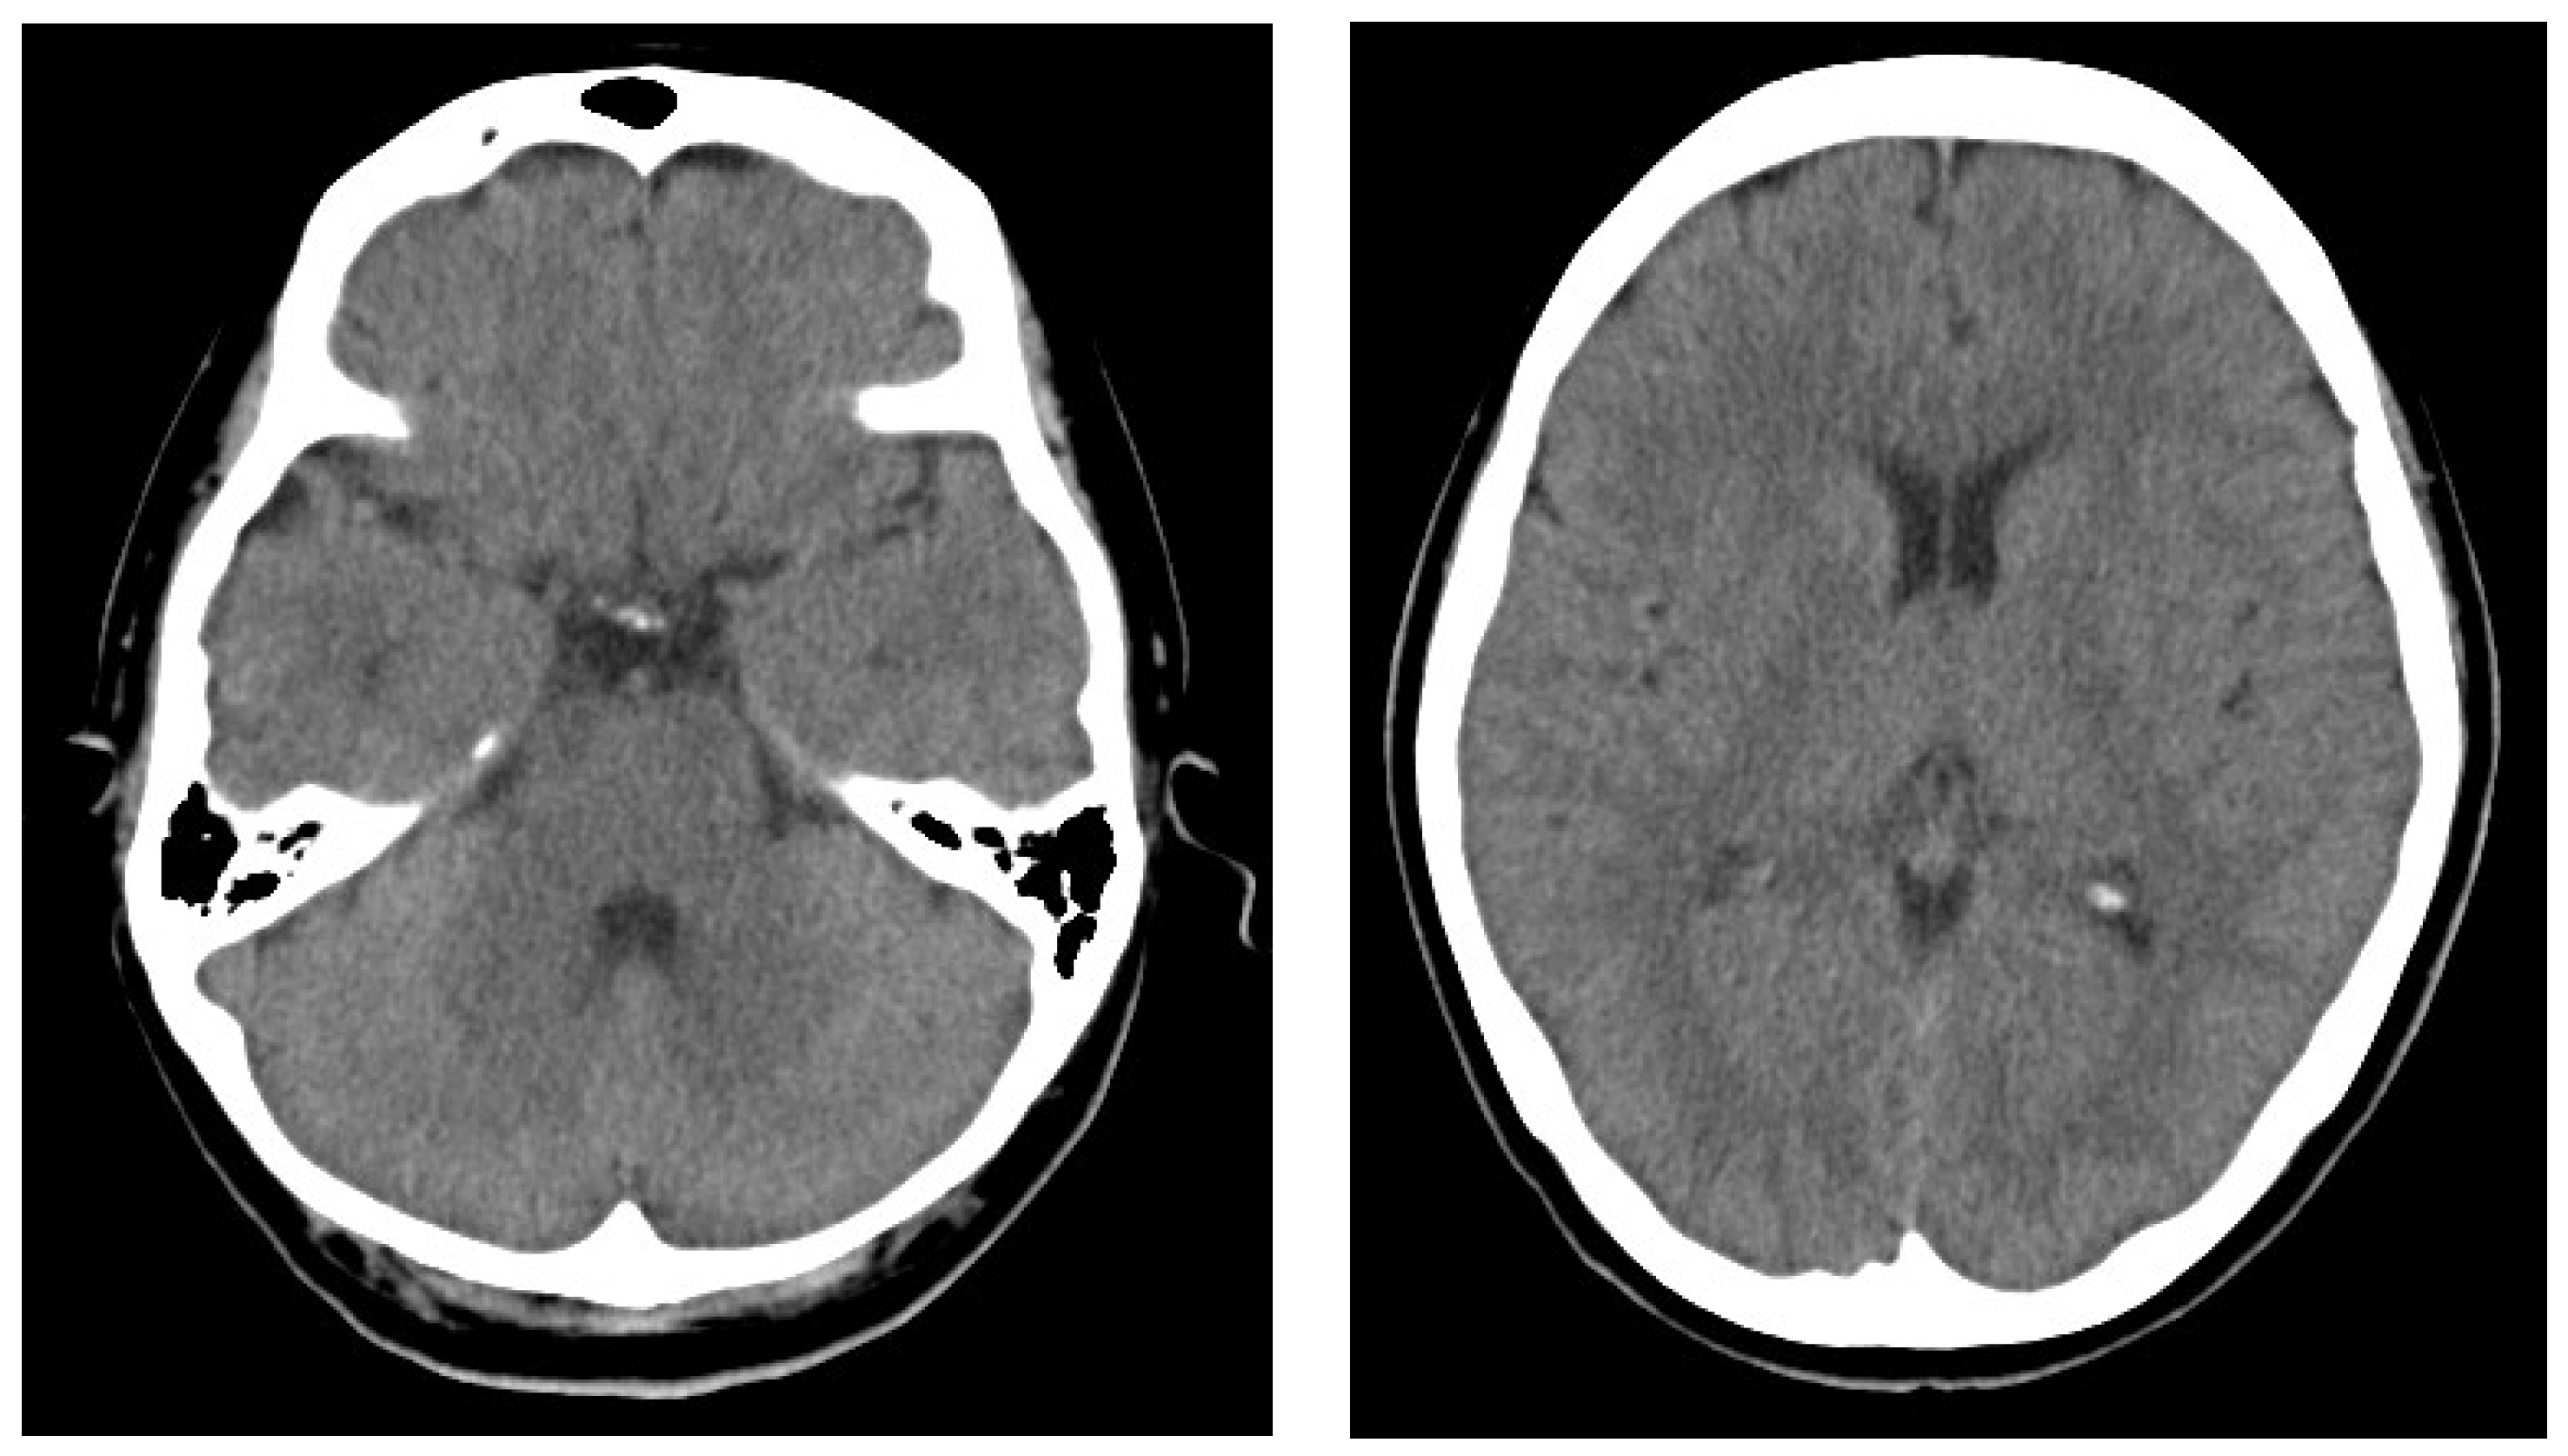

At her first medical visit at age 49, neurological examination showed no abnormality and the brain computed tomography (Figure 1) and routine blood tests were normal. No previous history of neurological or cardiovascular diseases has been recorded, and due to claustrophobia, an Magnetic Resonance Imaging test could not be performed. At that time, lomerizine chloride, an oral migraine preventive medication, was started at a standard dose. The symptoms showed a slight response to this therapy but did not completely resolve.

Figure 1. Brain CT.